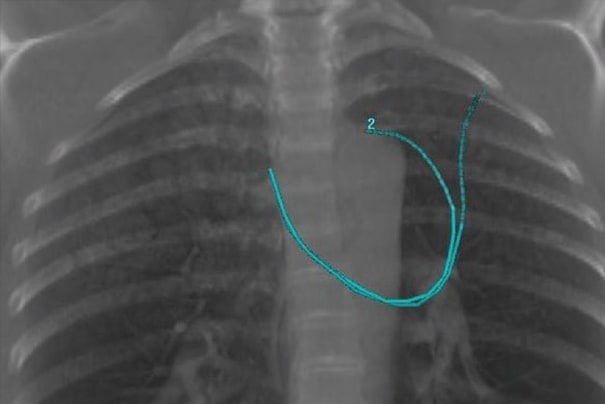

Bonvoisin-Gérard食道施源器设计用于帮助治疗内镜下食道阻塞。通过使用这种特殊的具有锥形柔性尖端的扩张施源器,可通过扩张探条到达治疗区域。探条管可使治疗导管内部居中,最大程度地减少粘膜受照剂量,同时确保食道壁获得最佳深度剂量穿透。探条管上的射线标记有助于通过荧光透视植入和定位施源器。

食道施源器设计用于直接插入食道以治疗食道癌。用户可在荧光透视或内窥镜检查下,经口植入该施源器。它有一个额外的外层,可降低食道粘膜的受照剂量并保护施源器的完整性。

对于支气管和食道癌,此步骤并非必要步骤。在某些情况下,需要进行CT成像,用于制定治疗计划。对于食道癌,这可能是一个标准计划。

LumenCare®施源器——图片由UZL Gasthuisberg(比利时鲁汶)提供